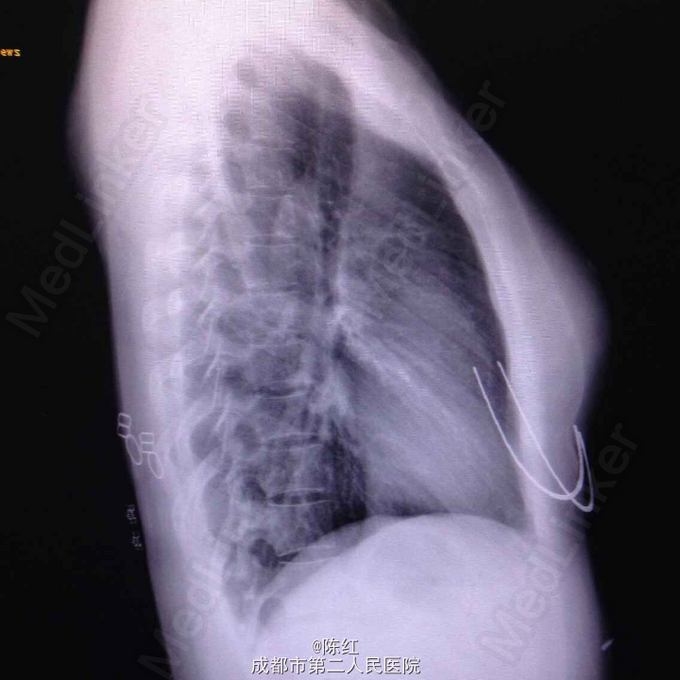

入院T37.49℃,P110次/分,R20次/分,BP108/70mmHg。神清,急性病容,皮肤黏膜未见黄染,全身无皮疹,双侧扁桃体Ⅱ度肿大,可见较多白色分泌物,颈部、双侧腹股沟可扪及数个肿大淋巴结,质软,活动,约1cm左右。双肺呼吸音清,未闻及干湿鸣,心律齐,未闻及心脏杂音,腹软,无压痛,双下肢无水肿。入院胸片未见异常。腹部彩超:脾脏稍长大。颈部彩超:双侧颈部淋巴结长大,咽拭子提示正常菌群生长,无真菌生长。痰培养正常菌群生长。EB病毒Ig M 109U/ml,Ig G 100U/ml,血常规:WBC13.29×10^9/L,N5.6%,L80.2%,异常淋巴细胞15%。生化:ALT 218U/L,AST 185U/L,心电图、心脏彩超、泌尿系+妇科彩超、输血前十项、免疫全套、肾功、电解质、血脂、血糖、血沉、PCT、凝血三项+D二聚体、大小便常规无明显异常。